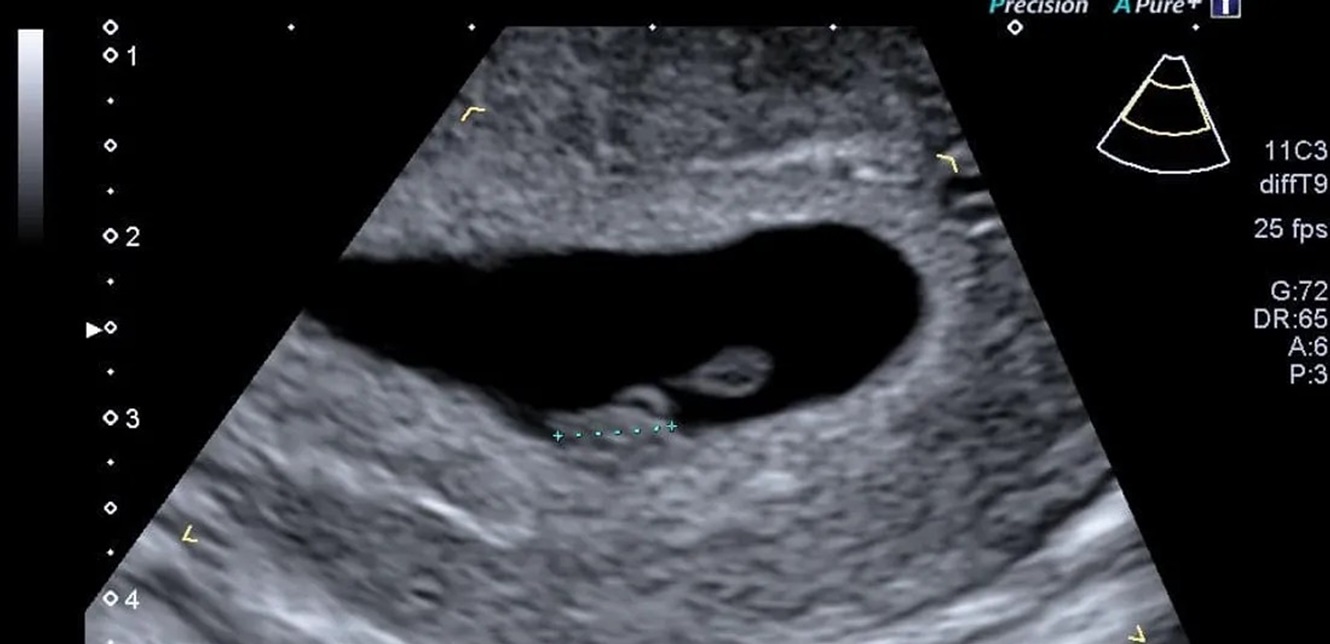

لكن مجموعة من الباحثين الأميركيين تقول إن استخدام الذكاء الاصطناعي لتحليل صور الموجات فوق الصوتية يمكن أن يتنبأ بموعد ميلاد الطفل بدقة تصل إلى 95 في المئة.

وباستخدام برنامج تم تطويره وتدريبه باستخدام أكثر من مليوني صورة بالموجات فوق الصوتية لنساء أنجبن أطفالهن بين عامي 2017 و2020، قام العلماء بقياس مدى قدرة الذكاء الاصطناعي على تقدير ما إذا كان الطفل سيرى النور في موعد ولادته أم لا.

أبرز نتائج البرنامج، المسمى Ultrasound AI:

التنبؤ بموعد ولادة الطفل في حالة الحمل المكتمل بدقة بلغت 95 في المئة.

التنبؤ بالولادة المبكرة بدقة بلغت 72 في المئة، من دون الحاجة إلى بيانات إضافية مثل التاريخ الطبي للأم أو القياسات السريرية.

التنبؤ بجميع حالات الولادة (بما في ذلك المبكرة) بدقة وصلت إلى 92 في المئة.

تعليقا على هذه النتائج، قال الدكتور جون أوبراين، مدير طب الأمومة والأجنة بجامعة كنتاكي: “الذكاء الاصطناعي بات يصل إلى داخل الرحم، ليساعدنا على التنبؤ بموعد الولادة بدقة، وهو ما سيقود إلى تحسين الرعاية الصحية للأمهات في جميع أنحاء العالم”. (سكاي نيوزو)